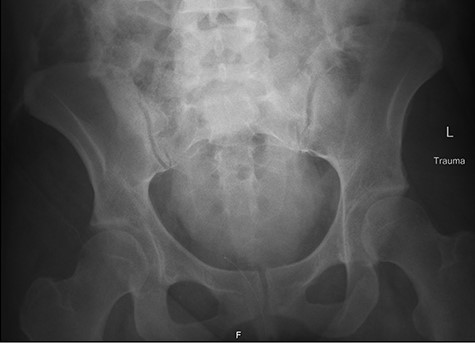

Right retrograde cystoscopy exhibiting extravasation of contrast.

Cystoscopy with retrograde pyelogram was performed by the urology team and this showed total disruption of the UPJ bilaterally with extravasation of contrast (Figs 3 and 4). She underwent bilateral interventional radiology nephrostomy tube placement. The definitive repair was planned for after pregnancy, but she required tube changes every 6 weeks. There was no fetal distress during her stay. She recovered well and was discharged after 5 days.